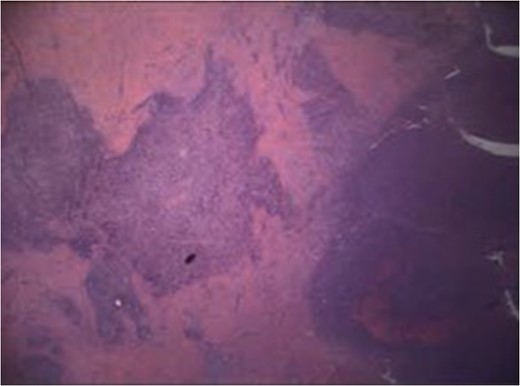

Pathologic exam revealed a resected portion of rectosigmoid that contained a diverticulum that had fistulized into the attached ovarian tissue, seen in Fig. 5. An adherent portion of fallopian tube was also present. The fistula tract was lined by granulation tissue with acute and chronic inflammatory cells and focal foreign body giant cells as seen in Fig. 6. The fistula extended into the ovarian stroma, causing a focal tuboovarian abscess. No other diverticula were present.

H&E slide, ×20 magnification. Fistula tract (left) lined by granulation tissue and inflammatory cells extending into ovarian stroma (right).